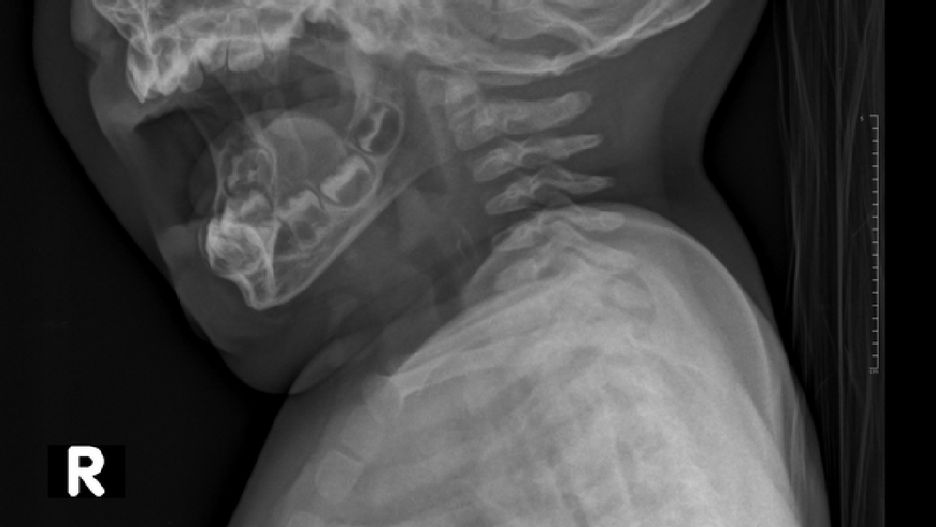

Do Szpitalnego Oddziału Ratunkowego zgłosiła się matka z 9-miesięczną córką, która wymiotowała i nie chciała nic pić. Początkowo nic nie wykryto. Dopiero kolejne badania wykazały, że dziecko połknęło małą naklejkę.

Dziewczynka wymiotowała i nie chciała pić. Początkowe badania nic nie wykazały, a naklejkę zauważono później.

Dziewczynka pobudzona, wymiotująca, występuje ślinotok, nie chce pić. Wykonano RTG, które nic nie uwidoczniło. Endoskopia uwidoczniła ciało obce — czytamy na profilu.